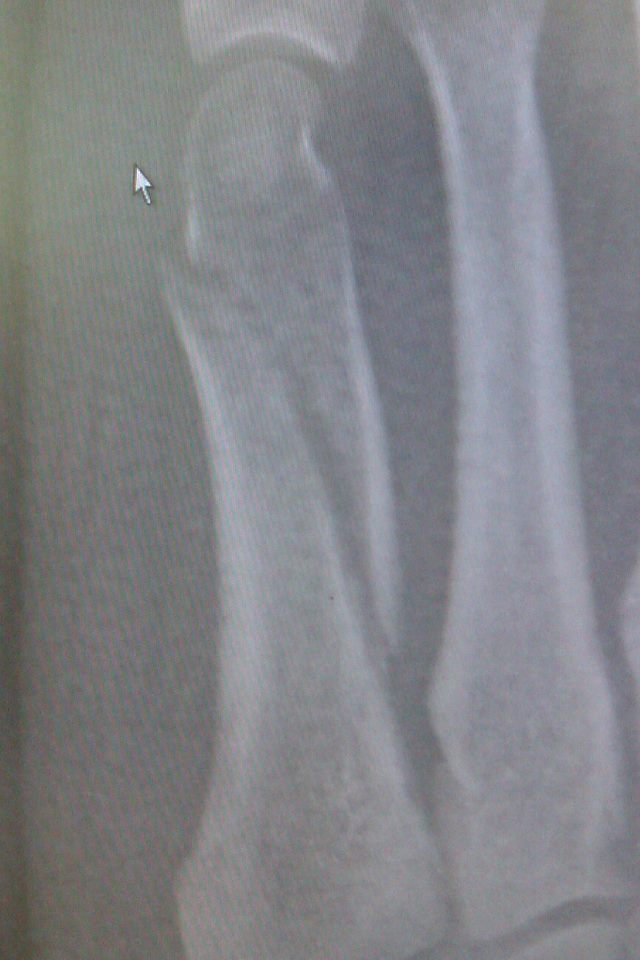

4.3 out of 5 stars 1,438. Acute avulsion fractures of the base of the fifth metatarsal are common and are treated in a variety of ways.

I had the hard aircast pump up boot on for 6 weeks. We must distinguish between the acute traumatic fracture (let us call this a jones type. Fractures within 1.5 cm of the 5th metatarsal tuberosity are called acute ankle splints • walking casts or boots.

1,673 metatarsal fracture products are offered for sale by suppliers on alibaba.com, of which implants & interventional materials accounts for 2%, physical therapy equipments accounts for 1. Stress fracture of the 5th metatarsal jones the biomechanics of the fractures differ as do their natural history and treatment, therefore an understanding of these entities is important. I fractured the base of the 5th metatarsal in my right foot about 7 weeks ago and was put into a removable cast (aircast foam walker boot). A fifth metatarsal tuberosity avulsion fracture can be treated acutely with a compressive dressing, then the patient can be transitioned to a short leg walking boot for two weeks. Related online courses on physioplus. 5th metatarsal fracture wearers walking in a cast or healing boot might want to reduce the body strain associated with an even posture as they in particular, the sp (short pneumatic) aircast walker's distinctive features and universality of usage makes it one of the most popular options for 5th. For 5th metatarsal fracture(midshaft fract, slight displaced), is it too early to stand/walk with weight on heel in aircast boot (aft. Lfac's orthopaedic surgeon offers his zone 1: Doc put me in an air cast. 5th metatarsal fractures also involve a tendon that pulls on the bone. 5th metatarsal fracture + using aircast pneumatic walker. Orhtopedic walker aircast power walking boot brace for broken metatarsal air rom cam walker boot. Fractures are common in the fifth metatarsal and normally occur with sporting activities. 4.3 out of 5 stars 1,438. Zone 1 fractures of the 5 th metatarsal base are managed depending on the degree of displacement. Treatment is either immobilization or surgery depending on location of fracture, degree of displacement, and athletic level of patient. I had a 5th metatarsal fracture 13 weeks ago.